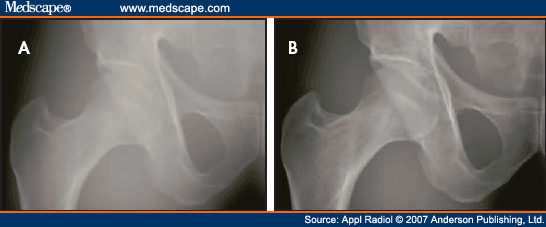

Pleural Effusion

What is the lung condition that causes an increase in fluid around the lungs requiring an increase in technique?